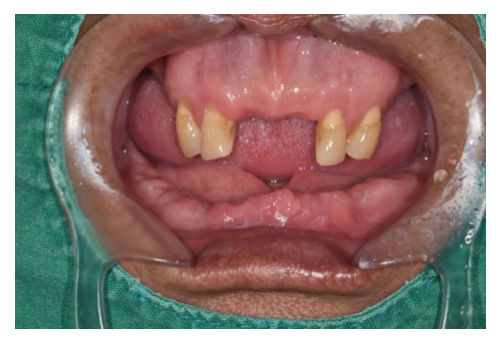

2 60대 남환 임플란트

• 상악 전체틀니 / 하악 부분틀니를 장착하고 계신 60대 남성 환자분입니다.• 뼈이식을 동반..